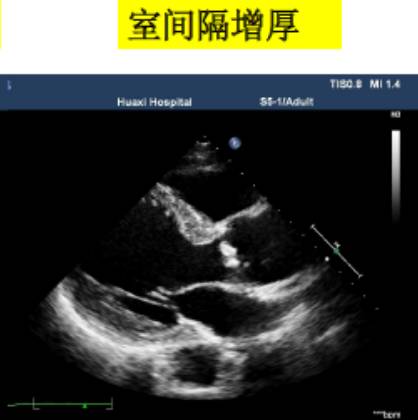

1、左心室径线的测量

测量位置:胸骨旁左心室长轴,或二尖瓣瓣尖水平左心室短轴切面。

测量内容:室间隔厚度、左心室后壁厚度、左心室内径。

测量时相:收缩末期、舒张末期。

直接二维测量或在二维引导下的M-型曲线上测量。

图|胸骨旁左心长轴切面,二尖瓣瓣尖水平。左图为舒张末期,右图为收缩末期。

随着图像处理技术的改进,已经提高心脏结构的分辨率。可按照真实的组织和血流的界面来测量室间隔和左心室后壁的厚度,而不是像以前测量前缘回声之间的距离。

ASE推荐于二尖瓣瓣尖水平胸骨旁短轴切面直接测量或采用M型曲线测量。M-型超声时间分辨率好。有助于帮助二维超声区分临近左室后壁的肌小梁、室间隔左室面的假腱索、室间隔右室面的调节束等结构。即使采用二维引导也可能无法保证M-型取样线完全垂直于室间隔和左心室后壁。